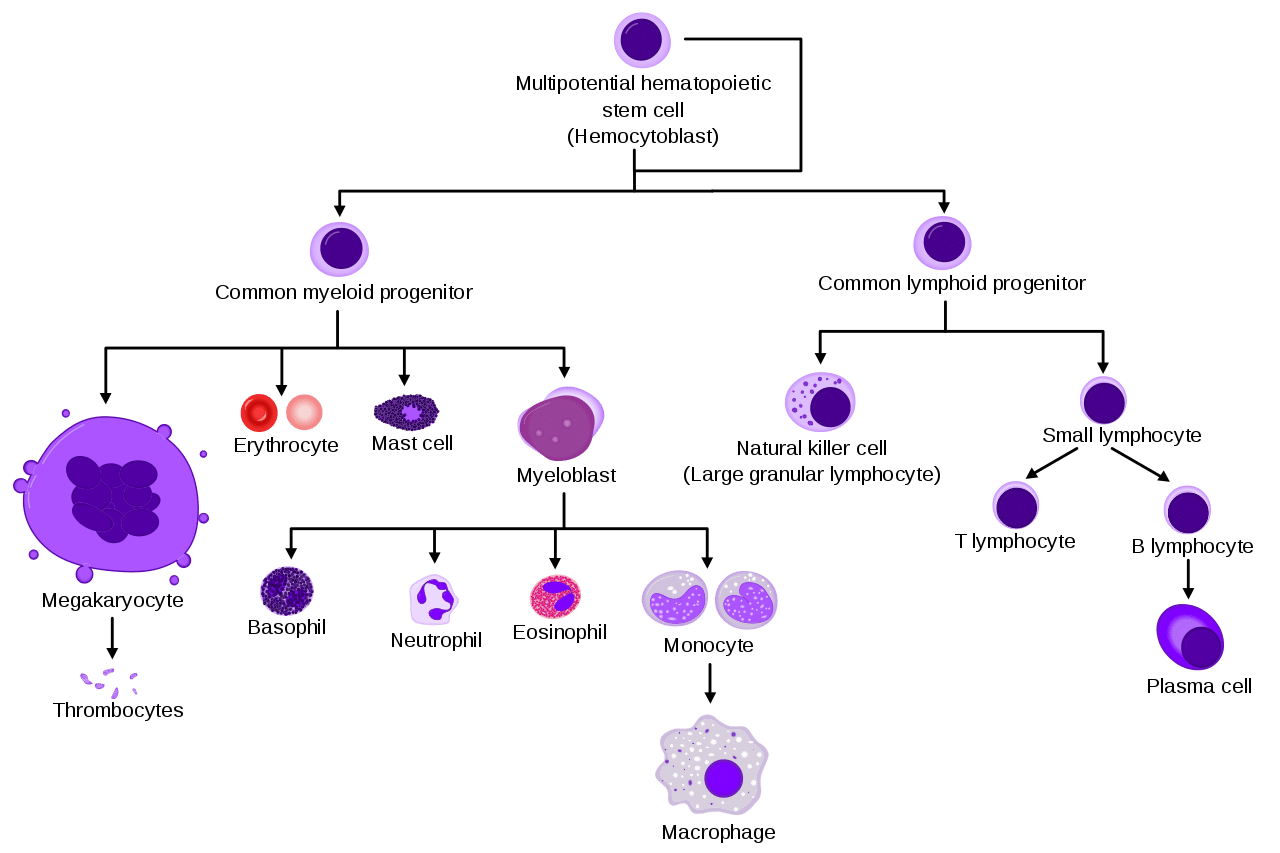

This diagram shows the formation and development of different types of white blood cells

This diagram shows the formation and development of different types of white blood cells